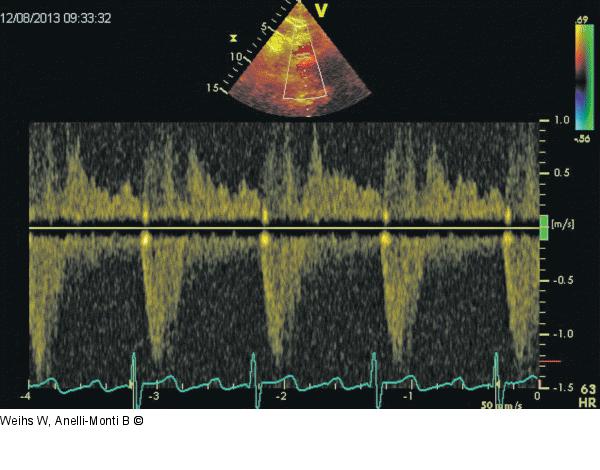

Abbildung 4: Holodiastolischer Rückfluss Der holodiastolische Rückfluss in der Aorta descendens spricht für eine hochgradige Aorteninsuffizienz. Darstellung von suprasternal. |

Der holodiastolische Rückfluss in der Aorta descendens spricht für eine hochgradige Aorteninsuffizienz. Darstellung von suprasternal. |